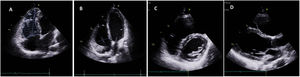

Clinical caseWe report the case of a 17-year-old federated soccer player who sought emergency care following an episode of palpitations and dizziness while playing soccer. He reported having already had two episodes of syncope upon exertion in the last six months but did not value them and therefore did not go to the emergency room. He denied any other personal history, regular consumption of drugs or narcotics and any relevant family history, including a history of SCD. The patient was tachycardic (218 bpm) and hypotensive (85/56 mmHg). A 12-lead ECG was performed which revealed wide complex tachycardia with left bundle branch block morphology and superior axis (Figure 1). Given the hemodynamic instability, the patient underwent electrical cardioversion with a biphasic shock of 50 joules and reverted to sinus rhythm. The ECG in sinus rhythm showed a T-wave inversion of V1–V5, with no other alterations (Figure 1). From laboratory tests, only a slight elevation of troponin I (0.97 ng/ml) was noteworthy. A transthoracic echocardiogram showed a non-dilated LV with good global systolic function, slight RV dilation and slight depression of its function (FAC) of 29%), with no other changes (Figure 2). The patient was hospitalized and underwent cardiac magnetic resonance imaging (CMR). CMR showed marked RV dilatation (end-diastolic volume indexed to body surface area of 180 ml/m2) by global hypokinesis with mild depression of its function (42%) and desynchrony. The late enhancement images showed subepicardial late enhancement in the distal septum and two small foci of subepicardial late enhancement in the middle segment of the inferoseptal wall (Figure 3). Thus, according to the 2010 TFC for the diagnosis of ARVC, the patient had three major criteria for the diagnosis of ARVC, including morphofunctional changes (areas of hypocontractility with a FAC ≤33%; desynchrony and RV end-diastolic volume indexed to body surface area ≥110 ml/m2), repolarization changes (inverted T-wave of V1–V5 in the absence of criteria for complete right bundle branch block), arrhythmia (sustained ventricular tachycardia with LBBB morphology and superior axis). Thus, taking into account that only two major criteria are needed for its diagnosis, the diagnosis of ARVC was made. Also, during hospitalization, the patient was implanted with a subcutaneous cardioverter-defibrillator (Figure 4). The patient remained asymptomatic throughout hospitalization. He was discharged with low-dose beta-blocker medication and contraindication for practicing sports. He is in regular follow-up in the Cardiology consultation, and adheres to the prescribed medication and recommendations, having, to date, no record of any new arrhythmic events. During follow-up, a genetic test was requested and enabled the identification of a pathogenic mutation categorized as associated to ARVC – variant c.1044_104dupAAAT (p.Asp350Lysfs*2) in the DSC2 gene which encodes the desmocholine-2 protein, and is implicated in the pathogenesis of ARVC. Thus, the patient has four major diagnostic criteria. A Holter was also requested which showed a number of ventricular extrasystoles >500 per day, fulfilling a minor criterion for the diagnosis. Currently, the patient does not participate in high-level sports nor any type of recreational sport.